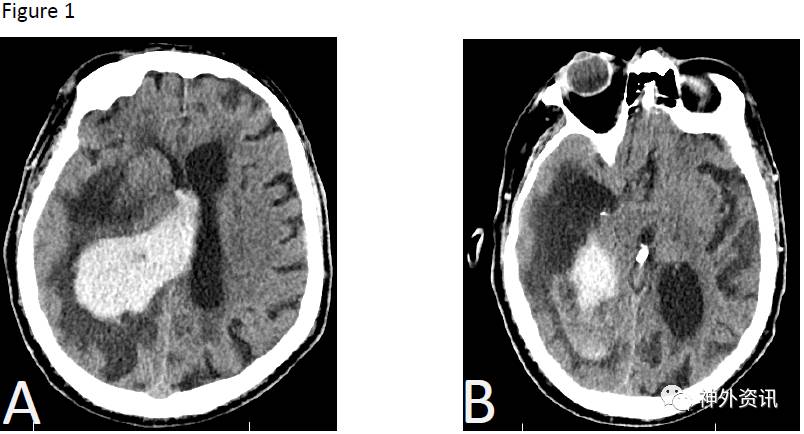

76岁男性患者,以精神状态改变和左侧肢体无力收治入院。头颅CT平扫显示右侧基底节区脑出血,血肿量达48ml,伴周围水肿和脑室内积血(图1)。术前将头颅CT扫描资料上传至ROSA系统,确定安全的穿刺轨迹与目标区域。患者全麻后,取仰卧位,头向左转45°。在ROSA系统帮助下,确定皮肤切口;颅骨钻孔后利用ROSA系统的peel-away鞘通过钻孔沿已定方向穿刺,按预先明确的深度达血肿腔。随后,置入引流管到血肿腔内进行引流(图2)。接着,采用同样方式将脑室外引流管放入右侧侧脑室颞角(图3)。术后头颅CT显示置管满意,颞角缩小。在术后48h内,通过导管向血肿腔注射2mg阿普替酶。经多次头颅CT扫描显示,血肿量逐渐减少到14.7ml、10.1ml,最终小于1ml。术后第三天将两根引流管拔除。

图1. 头颅CT平扫显示右侧基底节区脑内出血,伴周围明显脑水肿以及脑室内积血。